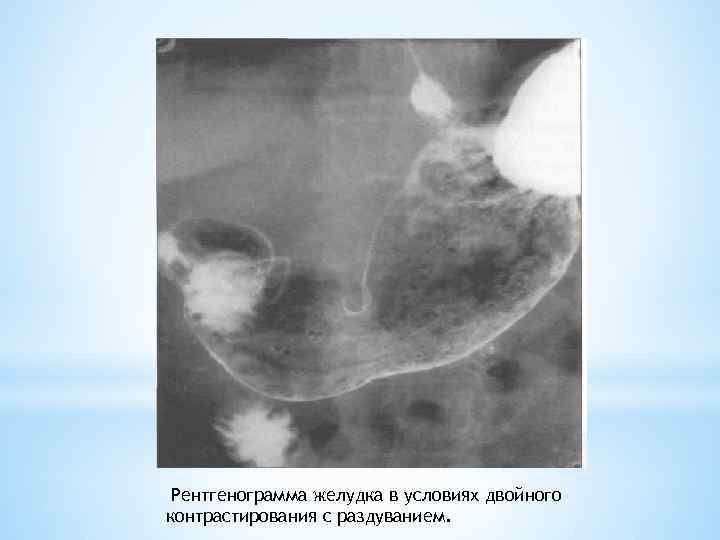

Рентгенограмма желудка в условиях двойного контрастирования с раздуванием.